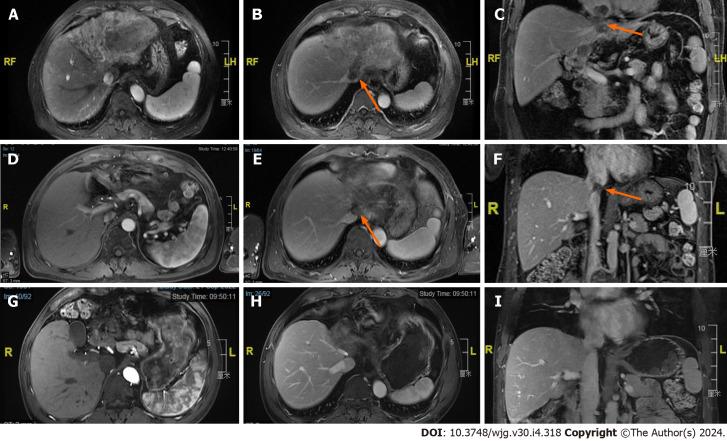

World J Gastroenterol. 2024 Jan 28;30(4):318-331. doi: 10.3748/wjg.v30.i4.318.

A total of 13 randomized controlled trials were included. HAIC alone and in combination with sorafenib were found to be effective treatments ( values for ORs: HAIC, 0.95; for HRs: HAIC + sorafenib, 0.04). After PSM, 176 HCC patients were included in the analysis. The triple therapy group ( = 88) had a longer median overall survival than the AIPB group ( = 88) (31.6 months 14.6 months, < 0.001) and a greater incidence of adverse events (94.3% 75.4%, < 0.001).